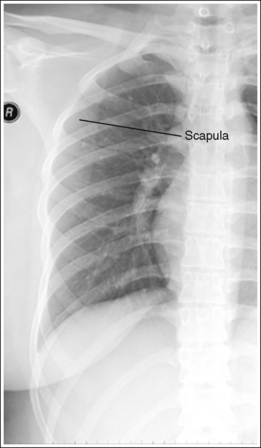

• Rotation versus scoliosis. In images of patients with spinal scoliosis, the ribs and vertebral column will appear rotated because of the lateral deviation of the vertebrae (see Image 9). Become familiar with this condition to prevent unnecessarily repeated procedures on these patients.

The scapulae are located outside the lung field, and the chin does not obscure the superior ribs.

• To avoid rotation, it is best to position the two arms in the same manner, even when only one side of the thorax is being imaged. If the scapula is not drawn away from the lung field, it is demonstrated in the upper ribs (see Image 10).

The distances from the vertebral column to the lateral rib edges down the length of the thoracic region vary, indicating that the patient has spinal scoliosis.

The left scapula is superimposed over the upper lateral rib field. The left elbow and shoulder were not rotated anteriorly.

If the patient's condition allows, place the back of the patient's hands on the hips, and rotate the elbows and shoulders anteriorly.